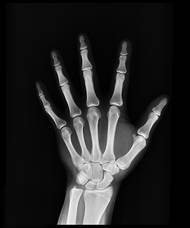

Nemocnice v Domažlicích hlásí novinku, v tomto týdnu zprovoznila vlastní pracoviště denzitometrie, kde se provádí měření hustoty kostí. Lidé z Domažlicka už tak nemusí na vyšetření čekat i několik týdnů a dojíždět až do Klatov nebo Plzně. Nemocnice pak ještě v první polovině roku připravuje otevření osteologické ambulance, která o pacienty s osteoporózou a metabolickým onemocněním skeletu pečuje.